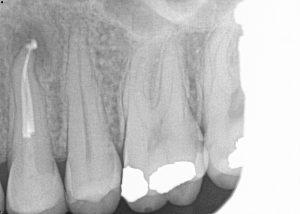

Root Canal / Retreatment

Apical Microsurgery / Apicectomy

Clinical Cases